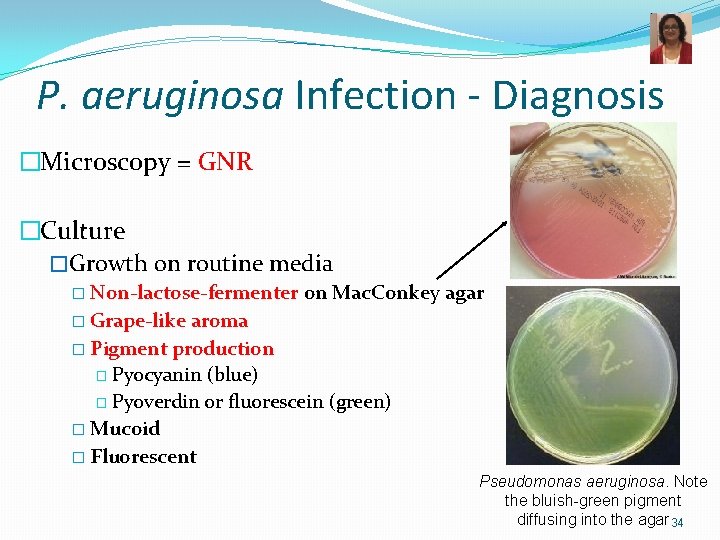

P. aeruginosa Infection - Diagnosis �Microscopy = GNR �Culture �Growth on routine media � Non-lactose-fermenter on Mac. Conkey agar � Grape-like aroma � Pigment production � Pyocyanin (blue) � Pyoverdin or fluorescein (green) � Mucoid � Fluorescent Pseudomonas aeruginosa. Note the bluish-green pigment diffusing into the agar 34